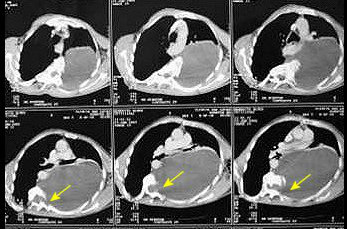

O estudo IFCT-0302 não demonstrou diferença na sobrevida global entre pacientes com câncer de pulmão não pequenas células completamente ressecadas que receberam tomografia computadorizada (TC) como parte de seu seguimento e aqueles que não realizaram o exame. Os achados serão apresentados no Congresso ESMO 2017, que acontece entre os dias 8 e 12 de setembro, em Madri, e sugerem que as tomografias computadorizadas regulares podem não ser necessárias1.